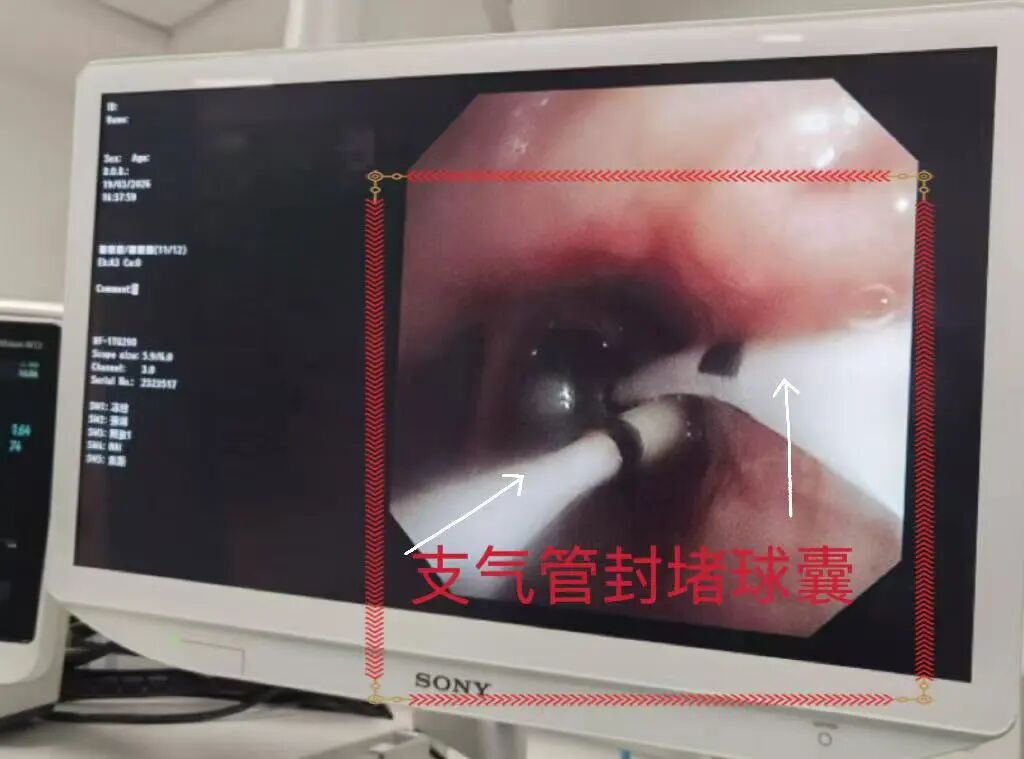

在科室副主任(主持工作)韩睿副主任医师的指导下,李江华副主任医师带领团队首先尝试经胸引管注入亚甲蓝进行瘘口定位,支气管镜下未能清晰显现。随即调整诊疗策略,采用多枚封堵球囊对右侧各级支气管分步封堵、逐一排查,最终明确瘘口并非位于手术支气管残端,而是累及右中叶、右下叶共5个亚段的复杂支气管胸膜瘘。

多枚封堵球囊分步封堵右侧各级支气管